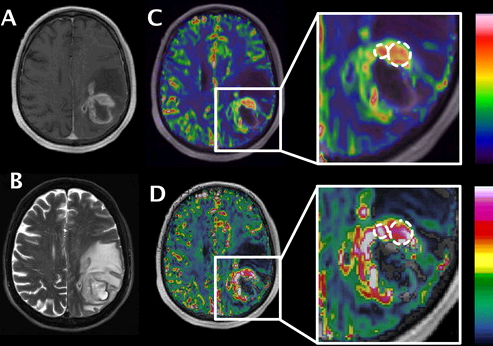

SyMRI 11.2 is now live! The latest update introduces reference curves as a new feature as well as improvements to T2-FLAIR weighted images. Read more here: https://syntheticmr.com/archive/articles/news/symri-11-2-released/ …

#SyMRI#NEURO#Radiology#NeuroRad pic.twitter.com/tvEQCD3nse